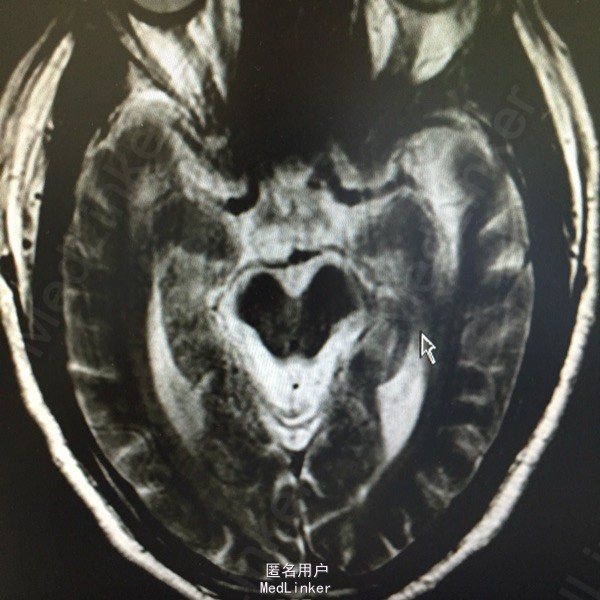

头痛伴视物双影5天。既往高血压、糖尿病、脑梗死。该患于入院前5日无明显诱因出现视物双影,偶伴头痛,不伴有恶心、呕吐,无视物旋转,无吞咽困难,病程中无肢体活动障碍,无言语不清,无意识障碍及尿便失禁。曾有中耳炎病史,伴有听力减退,曾于入院前3日在眼科医院激光治疗眼底出血。为求进一步诊治而来我院。

查体:神清语利,左眼内收受限,鼻唇沟对称,伸舌居中,双耳听力减退,肌力肌张力正常,双下肢病理症(-)颈强(-)。

诊断:脑梗死、高血压、2型糖尿病、高脂血症、中耳炎 治疗:营养神经、改善循环、神经生长因子、降脂、抗炎对症治疗。